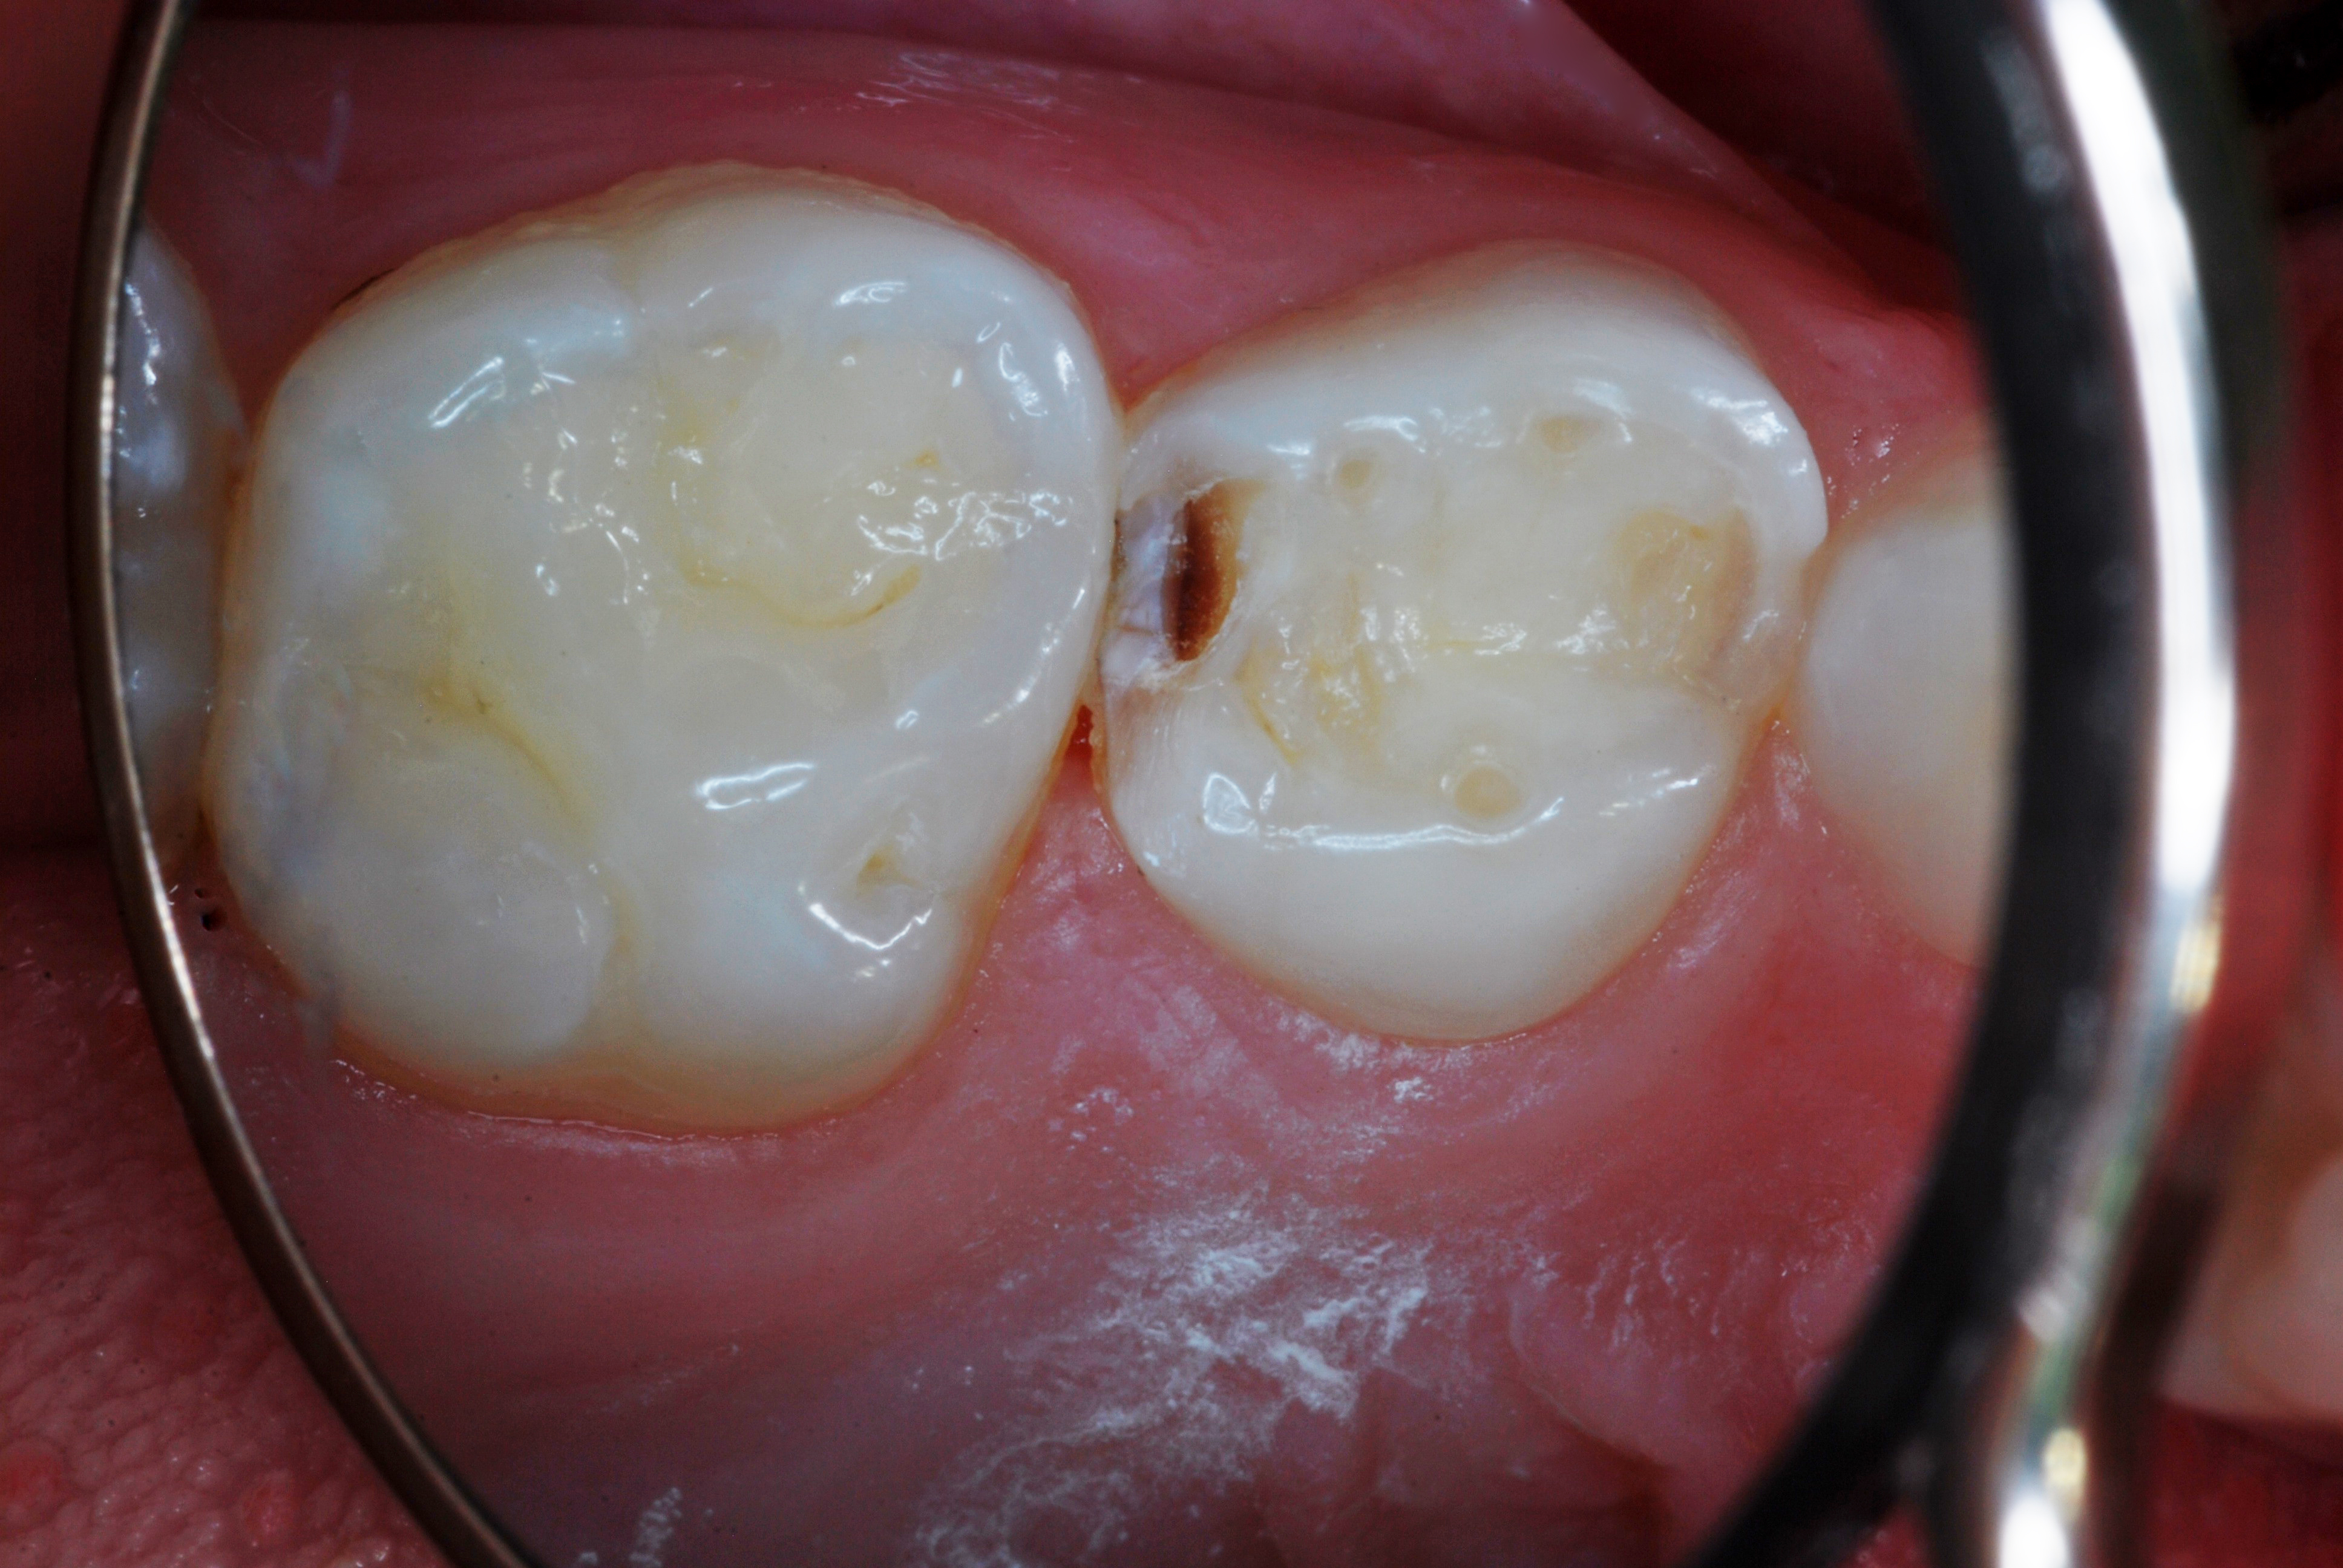

(1.) Hypocalcified/carious first molar, 12 months after SDF application.

Figure 1